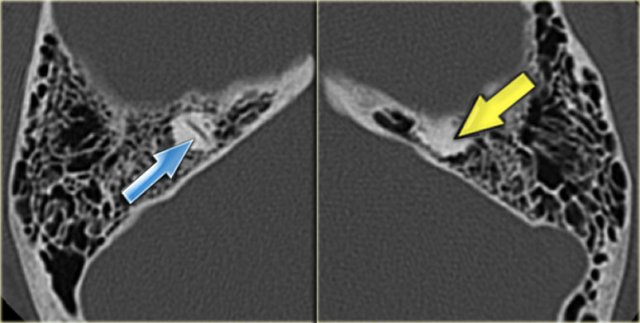

On the left a 16-year old boy, examined preoperatively for a cholesteatoma of the right ear.

As a coincidental finding, there is a plump lateral semicircular canal (yellow arrow) and an absence of the superior canal (blue arrow).

In the expected position of the superior canal only a bump is seen.

The posterior canal is normal.